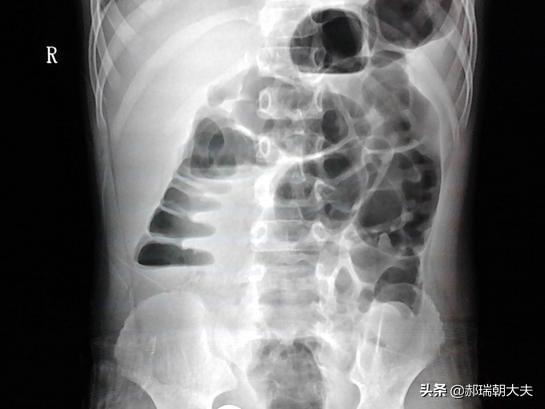

Bien entendu, cela ne se produit généralement pas, mais seulement dans le cas d'une occlusion intestinale, lorsque l'intestin est obstrué pour diverses raisons et que le contenu proximal de l'occlusion ne peut pas être drainé vers le bas.

Les symptômes typiques de l'occlusion intestinale sont la douleur, les vomissements, la distension et la fermeture ; douleur : douleur abdominale ; distension : ballonnement abdominal ; fermeture : pas d'évacuation des gaz et pas de selles ; vomissements : vomissements, avec le contenu des aliments de la nuit, avec une odeur fécale si l'occlusion est faible, et une odeur acide si l'occlusion est forte.